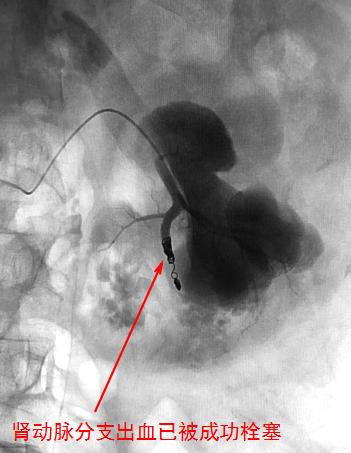

因此,对于大量尿血的处理也相对简单。内科治疗无效而又不必外科手术的,就可以进行介入诊疗。一般经股动脉穿刺入路,进行肾动脉造影找出是哪一支或哪几支动脉血管出血,然后即可对这些分支血管进行栓塞,疗效是有保证的。介入诊疗的好处是能最大限度地保护肾脏,从而免除迫不得已切除创伤肾所带来的巨大损失。

血尿的介入治疗

值得注意的是,肾动脉的发育变异并不少见,一侧肾有可能有2~3支肾动脉。所以在肾动脉造影前,先进行主动脉造影就显得有必要,从而不致于漏栓那些出血的责任血管。如果介入诊疗*考前**虑出血来源于膀胱(如由膀胱癌引起),双侧髂内动脉造影必不可少;之后再根据造影结果对膀胱上动脉等可能的责任血管进行栓塞。